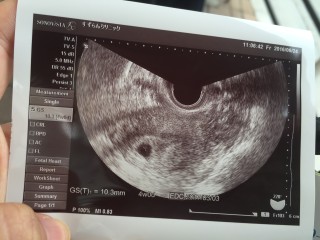

最終月経から数えて6週6日目だったので心拍確認できるかな?と思ったらGS10.3mmで4週0日程の大きさと言われました……。おそらくずっとトリキュラー28飲んで、止めてから1度も生理来てないし、周期が乱れたんだと思います。排卵日が定かではないので…。もし4週目ならば3週目に陽性くっきりということになります。 でも、最近茶オリも出てきたので、まさか不成長か流産??と思いましたが、2週間後の検診まで信じます。

最終生理日からだと6wですが、エコーでみると4wと先生から教えてもらいました(^-^) 想像していたより大きさが小さくて不安になりましたが、ちゃんと正常妊娠とのことだったので、安心しました(^-^) 次ゎ2週間後と言われてからそろそろ1週間(*^^*) あと1週間までが待ち遠しいです(*^^*) 無事に育っていますよーに>_<♪